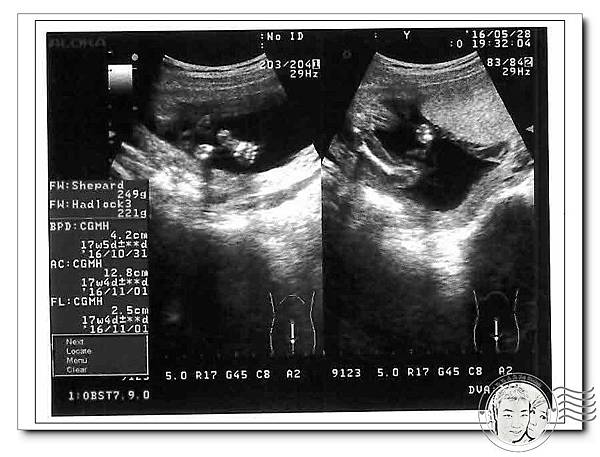

高層次超音波~禾馨民權婦幼診所~21週